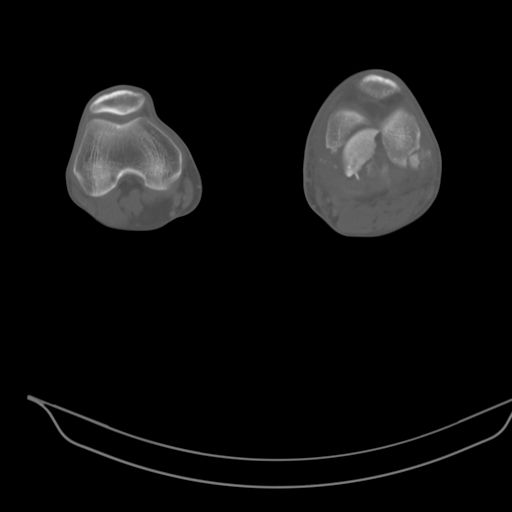

This is a coronal split in the femoral condyle and is a rare injury. Please see attachment for ORIF result

CT shows major bony fragments which are markedly rotated .With this amount of bony damage,you probably should attempt to get reasonably loooking knee with ORIF and thn if he needs a TKR due to pain a few years from now, then tleast you have something looking like a knee that you can replace rather than having to use revision knee for a primary TKR now. 4 weeks is not too long .what is the condition of soft tissues?

При внутрисуcтавных переломах трехмерные (3D) изображения, кроме красивого снимка, не дают полную информацию о состоянии отломков, самыми информативными являются корональные срезы на КТ и обычная длинная ренгенограмма конечности для сравнения оси конечности.

Фронтальные внутрисуставные переломы мыщельков бедра, так называемые Hoffa fracture, не частые, но встречающиеся переломы, в основном они связаны с травмой высокой энергией.

В зависимости от смещения рекомендуется сопоставление костных фрагментов с последующей жесткой фиксацией.

В вашем случае доступ будет медиальный, сопоставить развернутый медиальный мыщелок и фиксацию надо произвести в передне-заднем

направлении шурупами 4.5 мм в диаметре, углубив головку шурупов под хрящ, а поперечную фиксацию - межмыщелковыми шурупами. Желательно применить шурупы 6.3 мм в диаметре. Дополнительная Buttress technique пластина предотвратит перелом от скольжения.

Даже при сросшемся переломе мыщелка рекомендуется реконструктивная операция для предотвращения последующих варус или вальгус деформации.

Место образовавшего костного дефекта после разворота мышелка заполняется спонгиозной аутокостью. Костная пластика применяется даже

в свежем случае.

Под наркозом редрессация, ранняя разработка сустава после операции, нагрузка на конечность через 12 недель помогут удержать без коллапса

фиксацию и поможет больному восстановить функции конечности без артропластики коленного сутава.